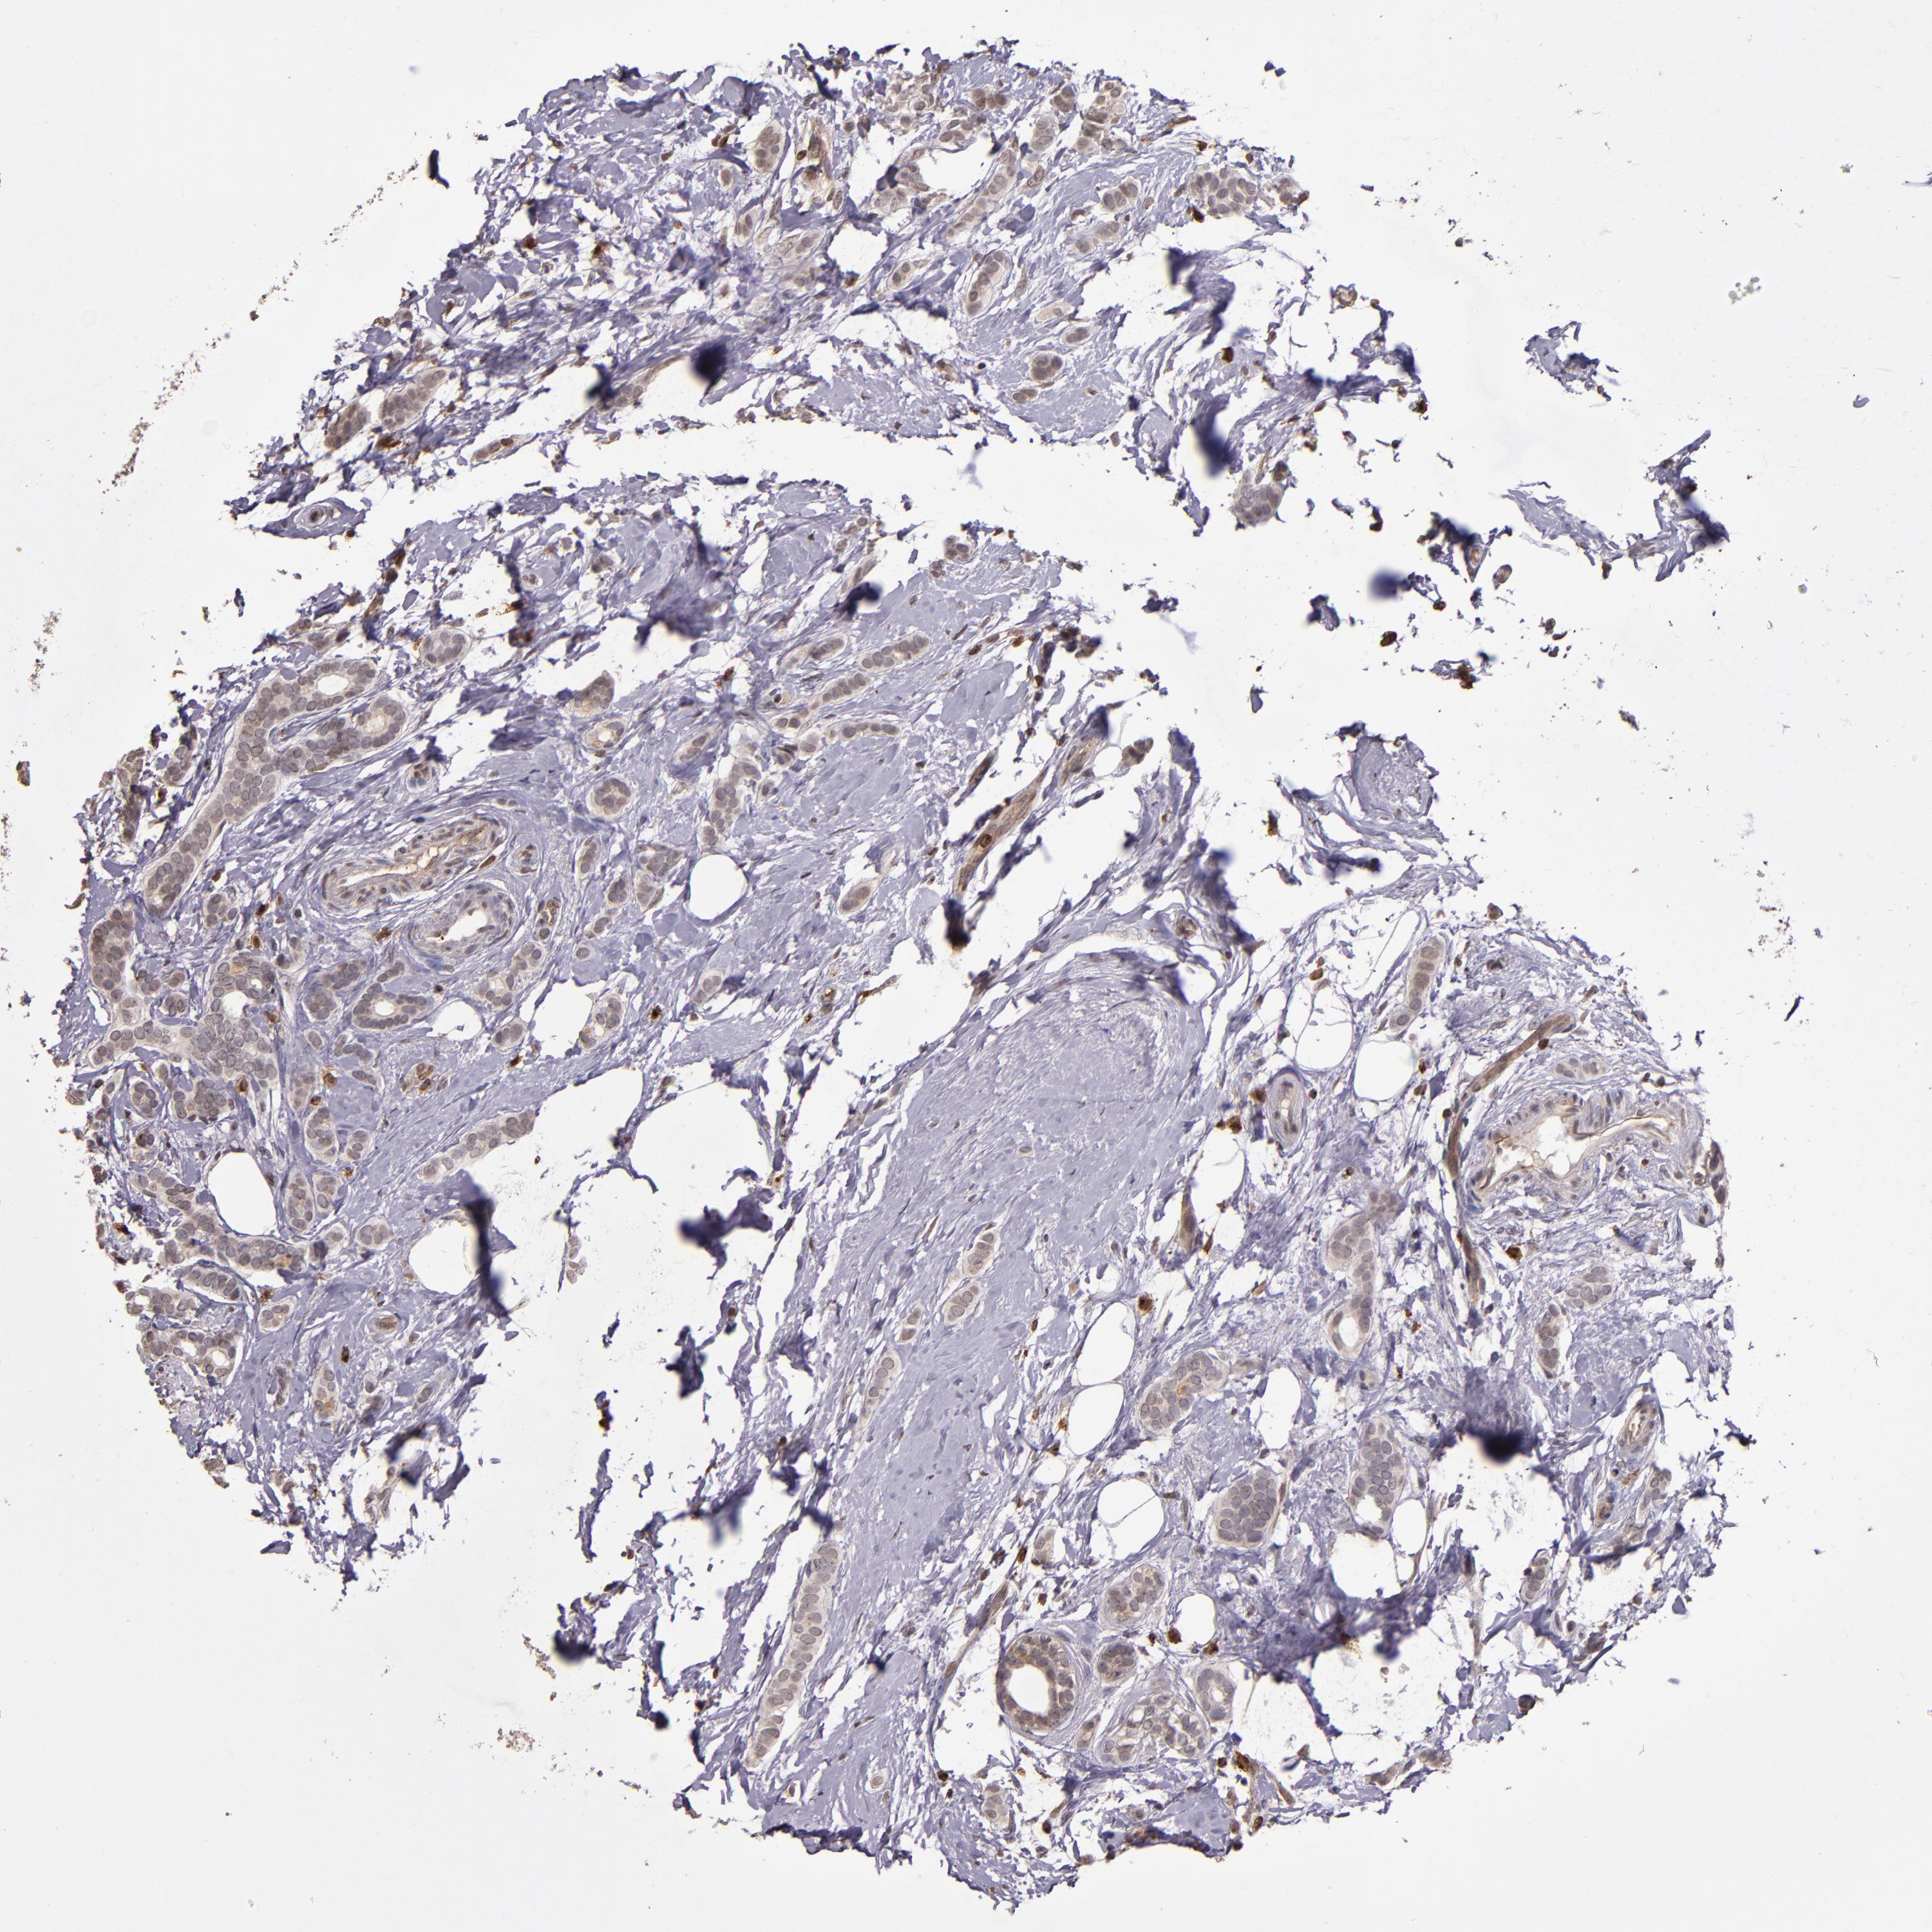

CANCER BREAST CANCER Show tissue menu

BRCA TCGA BRCA VALIDATION PROTEIN EXPRESSION

Breast cancer

Human cancer